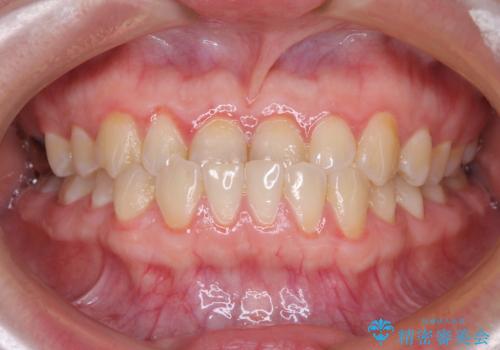

- 前歯の反対咬合を気にして来院された患者様です。

当院にて同様の咬み合わせを治療した方からのご紹介ということもあり、ご紹介者と同じワイヤー矯正で早めに治療を終えることを希望されました。

骨格的に下顎が前方に位置していましたが、歯列矯正で改善できると判断し、ワイヤー装置にて矯正治療を行うこととしました。

このような咬み合わせの方の多くは、舌の突出癖が強い傾向にあり、反対咬合改善後に開咬となってしまい、なかなか治療が終わらないことがあります。

こちらの患者様は、舌のトレーニングを治療開始前から徹底的に実践していただき、僅か8ヶ月という短期間で治療を終えることができました。